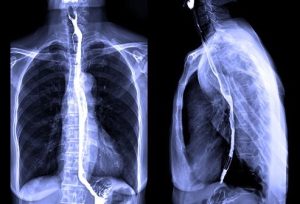

اشعه ایکس قفسه سینه (Chest x-ray)

رادیوگرافی قفسه سینه ممکن است برای مشاهده اینکه آیا سرطان به ریهها گسترش یافته است یا خیر انجام شود اما اغلب از سی تی اسکن ریهها استفاده میشود زیرا این روش تمایل به ارائه تصاویر دقیق تری دارد.